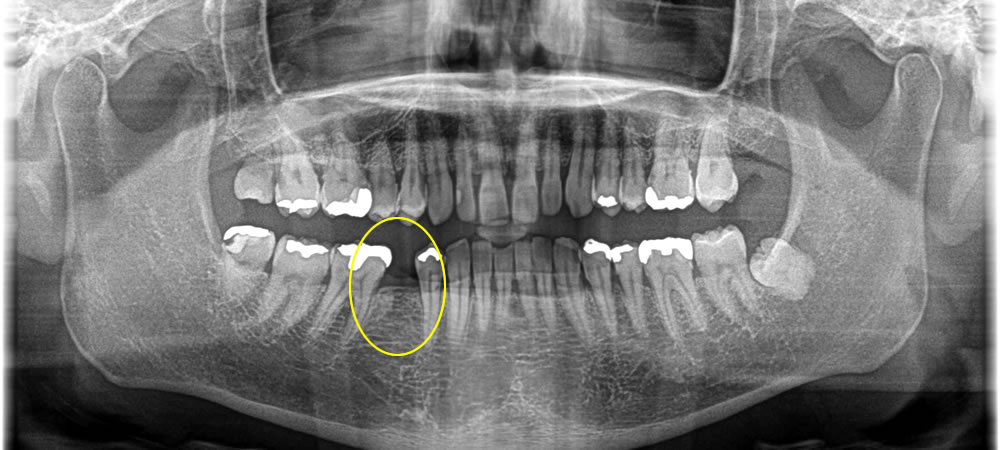

インプラント治療で抜歯した部分の咬み合わせを回復した症例

年齢

50代

性別

男性